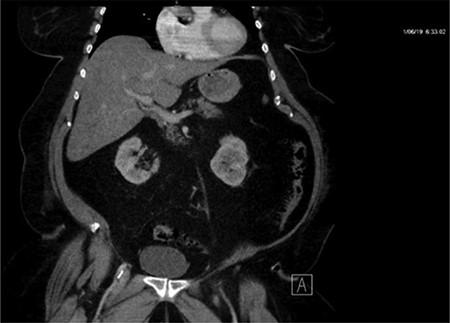

CT of the abdomen and pelvis with IV contrast was performed within 2 h of presentation. The scan showed “indeterminate, scattered ill-defined hypo-enhancing lesions in the liver with no acute etiology identified to explain the patient’s abdominal pain” (Figs 1, 3, 5). The remainder of the CT was unremarkable. Ultrasound (US) of the abdomen was negative. Because the CT and US did not identify an etiology for the patient’s abdominal pain, the working diagnosis at that time was an intestinal obstructive process.

CT with IV contrast taken at 0633 which shows ill defined, hypo-enhanced lesions of the liver.